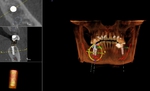

CT Scanner for Optimal Treatment Planning

New iCAT CT scanner offers precise imaging with radiation comparable to traditional x-ray units.  Using this 3D imaging technology the doctor can accurately plan surgery, avoid complications, and create custom implant treament plans.

The CT scanner's imaging allows us to create custom made surgical guides specific to each patient.  These surgical guides allow the precise placement of dental implants for optimal functional and esthetic results.

CT Guided Custom Implant Placment